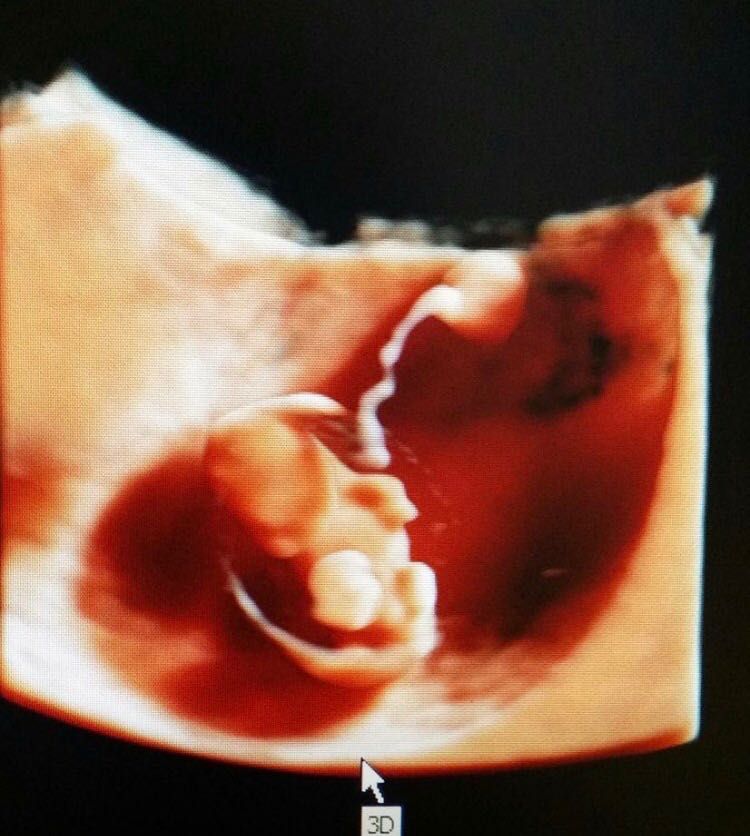

Mi sono sempre dedicata all’ecografia sia ostetrica che ginecologica. Seguo da sempre con dedizione le gravidanze, occupandomi anche dell’aspetto ecografico, come translucenza nucale, morfologica, eco 3D e 4D

Ecografia 4D

120 € -

Visita ostetrica + ecografia